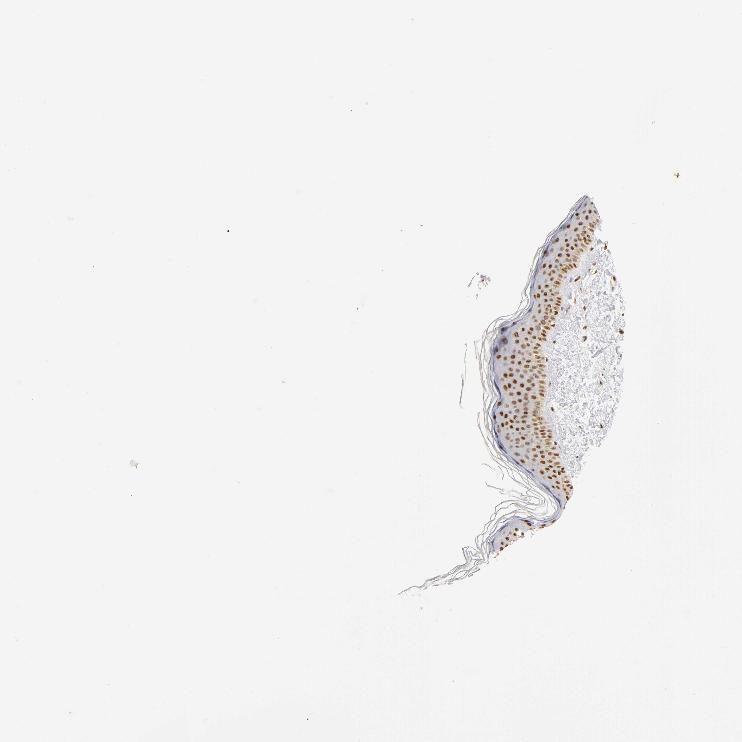

SKIN 1 - Antibody stainingi

Antibody staining in the annotated cell types in the current human tissue is reported as not detected, low, medium, or high, based on conventional immunohistochemistry profiling in selected tissues. This score is based on the combination of the staining intensity and fraction of stained cells.

Each image is clickable and will lead to virtual microscopy that enables deeper exploration of all samples and also displays staining intensity scores, fraction scores and subcellular localization as well as patient and tissue information for each sample.

Antibody HPA003888

Langerhans High

Fibroblasts High

Keratinocytes High

Melanocytes High

SKIN 2 - Antibody stainingi

Epidermal cells High